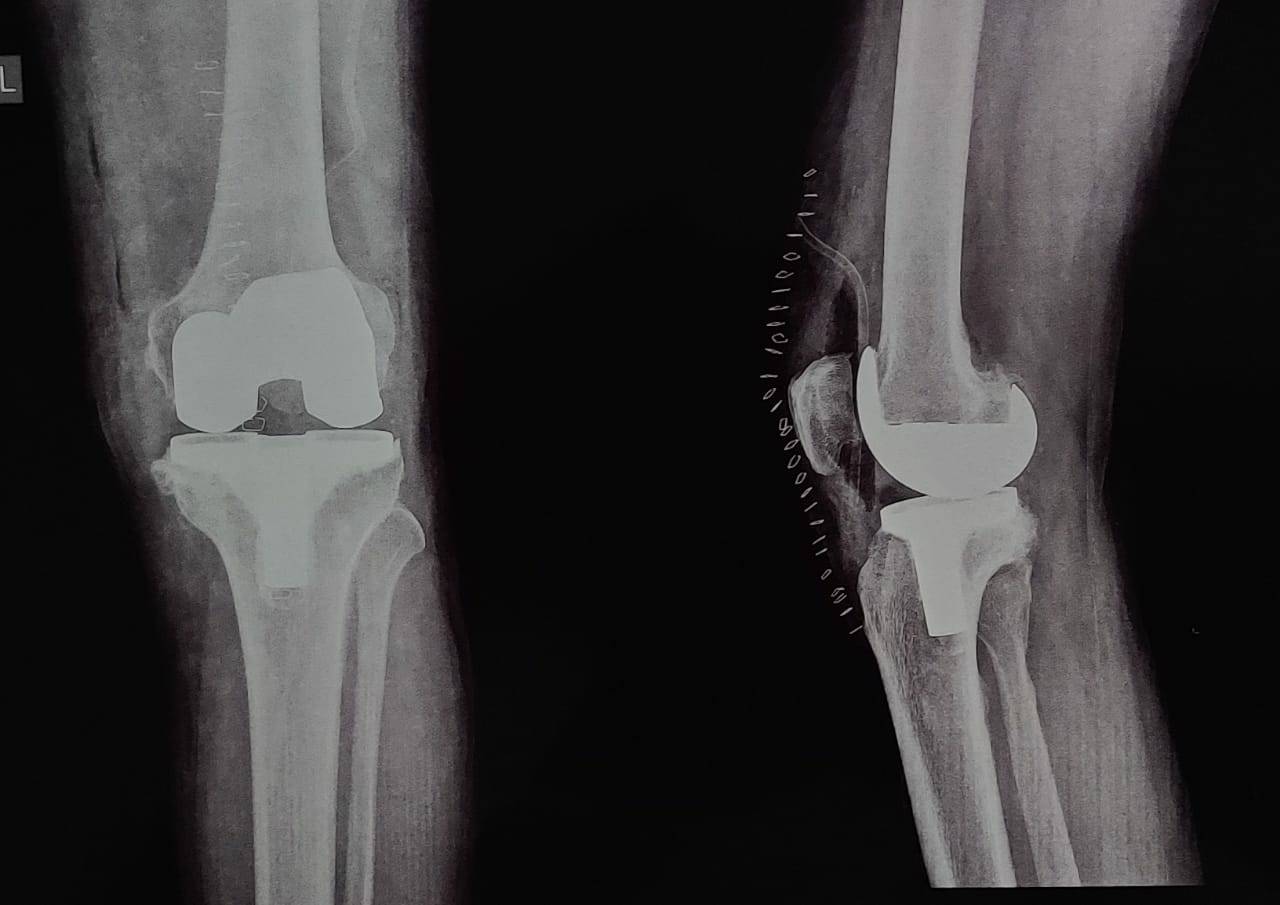

Knee replacement surgery- Degenerative osteoarthritis of knee is disabling painful knee condition . Give yourself a chance to have pain free life! Don't suffer knee pain Our clinic is offering knee pain camp from 11 Nov to 20 Nov.2021. Contact - 9765494689 for further assistance and appointment.